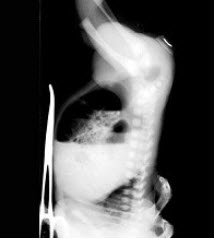

9、单项选择题

男,32岁,中上腹空腹痛,进食后缓解,剑突下轻度压痛,钡餐检查如图,最可能的诊断是()

A.十二指肠癌

B.十二指肠憩室

C.十二指肠球部溃疡

D.十二指肠节段性肠炎

E.十二指肠结核